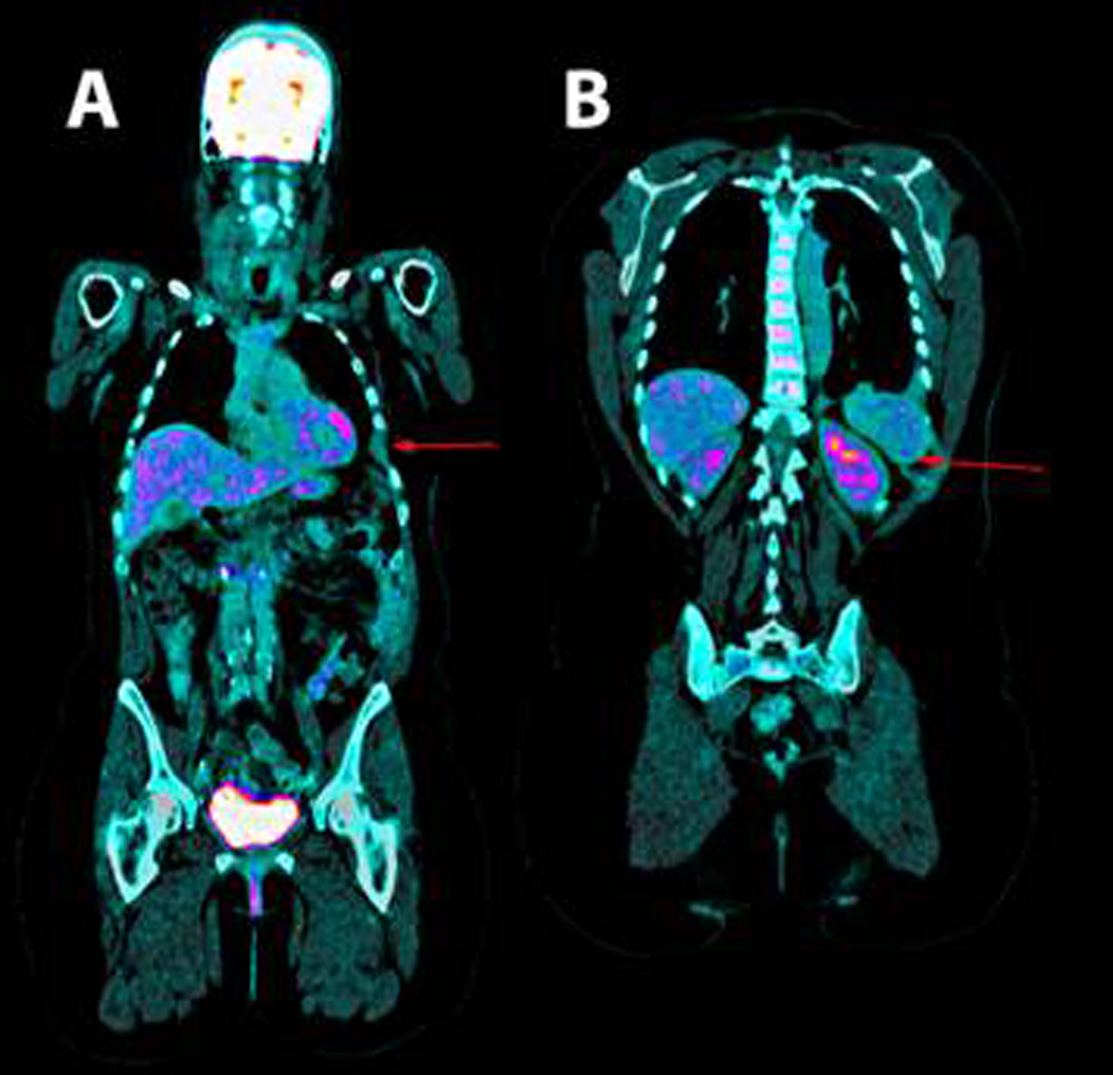

Thoracentesis was performed for evacuation with output of serosanguineous fluid with the following analytical data: glucose 97 mg/dl, LDH 179 UI/l, erythrocytes 571100/ μL, leukocytes 11620/ μL (3% polymorphonuclear, 97% mononuclear), proteins 5.3 g/dl, pH 7.43, rheumatoid factor 9.1 UI/ml, amylase 27 UI/l, cholesterol 86 mg/dl, triglycerides 26 mg/dl, adenosine deaminase (ADA) 13 UI/l. Negative flow cytometry of the pleural fluid for lymphoid infiltration. Cytology of the fluid without cellular atypias. Cultures of the pleural fluid for bacteria, mycobacteria, parasites and fungi were negative. Also, the Mantoux test and the gamma interferon test with quantiferon-TB(r) were negative for latent tuberculosis infection. The serology tests for hepatotropic viruses and human immunodeficiency virus (HIV) were negative. The mammography and the gynecologic ultrasound were normal. Both the bone scintigraphy (Fig. 2) and the CT scan (Fig 3), thoracic MRI and PET revealed hypoplasia and an osteolytic lesion in the 10th and 6th left rib arches together with effusion, significant left pleural inflammation and involvement of adjacent soft parts.

Figure 3. Positron emission tomography. A. shown the absence of the 6th and B. 10th left ribs arches.